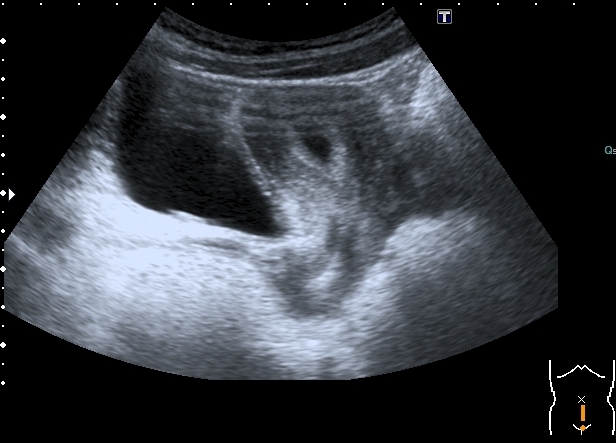

Увеличенная матка с анэхогенным содержимым в полости